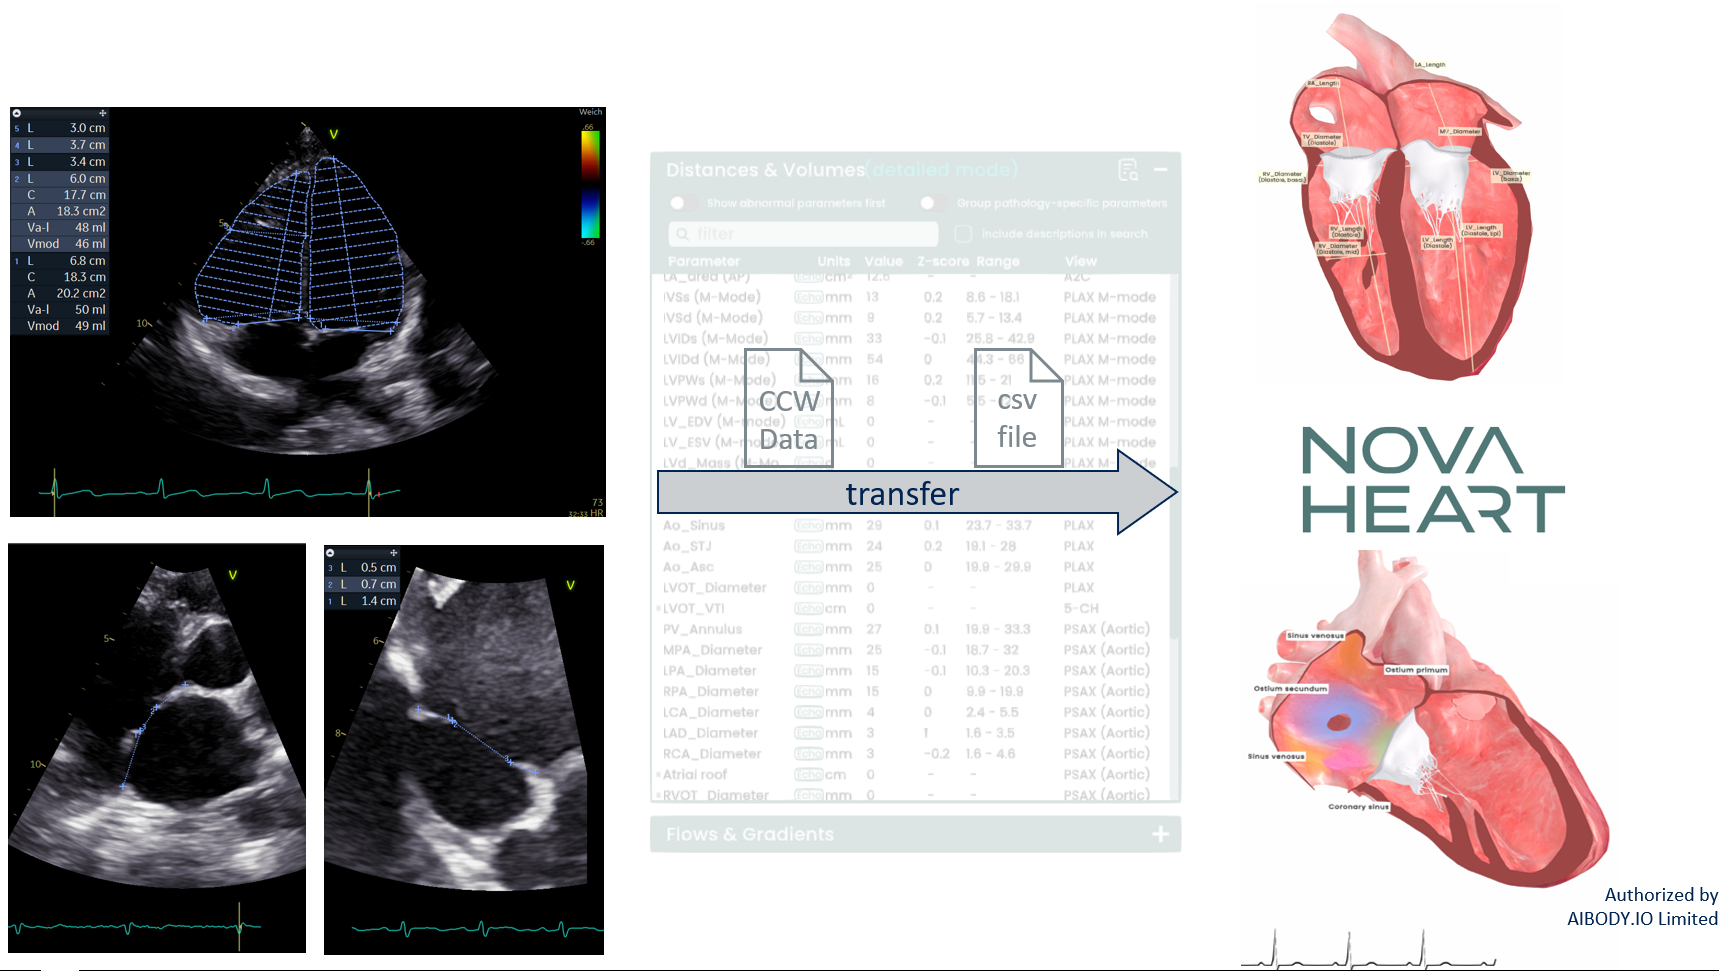

Digital Transformation of Echocardiographic Data: Accuracy and Innovation in 3D Hemodynamic Simulation for Atrial Septal Defect Assessment

Two-dimensional transthoracic echocardiography (2D TTE) remains the primary imaging modality in congenital heart disease (CHD) due to its accessibility, low cost, real-time functional assessment, and absence of radiation. However, 2D TTE lacks spatial resolution and is inherently operator-dependent, limiting consistent evaluation of structural lesions. To address these limitations, we developed an AI-assisted software that converts standardized 2D TTE data into interactive 3D hemodynamic models, enabling visualization and simulation of shunt volumes in atrial septal defect (ASD) patients. A dedicated acquisition protocol was implemented to improve reproducibility and reduce user dependency.

To validate the accuracy of this novel 3D simulation tool by comparing its Qp:Qs calculations to standard echocardiographic estimates, and to evaluate its potential for clinical, educational, and procedural applications.

We included 82 patients with a median age of 6 years (range 0.6–70 years) and a mean weight of 35 kg (range 5–100 kg), all referred for ASD closure. Standard 2D TTE was used to calculate Qp:Qs by measuring outflow tract diameters and subvalvular velocity-time integrals. The same echocardiographic datasets were used to generate individualized 3D heart models with simulated shunt volumes. The software-calculated Qp:Qs values were compared to echo-derived estimates using Spearman’s correlation coefficient.

The mean deviation between the software-generated Qp:Qs ratio and the echocardiographically estimated value was +3% (SD ± 32.4%). A statistically significant correlation was observed between both methods (r = 0.403, p < 0.001). Visual assessments confirmed excellent topographic rendering of septal defects and intuitive interface usability for clinicians.

This study confirms the technical feasibility and diagnostic validity of transforming 2D echocardiographic data into functional 3D simulations for ASD evaluation. The statistical correlation with conventional Qp:Qs estimates suggests that such software tools can augment clinical workflows, reduce operator dependency, and provide a foundation for patient-specific simulation in CHD care. Beyond diagnostic applications, this platform offers translational value in education, patient counseling, and virtual preprocedural planning. A prospective multicenter validation comparing simulation results to catheter-derived Qp:Qs values is currently underway.